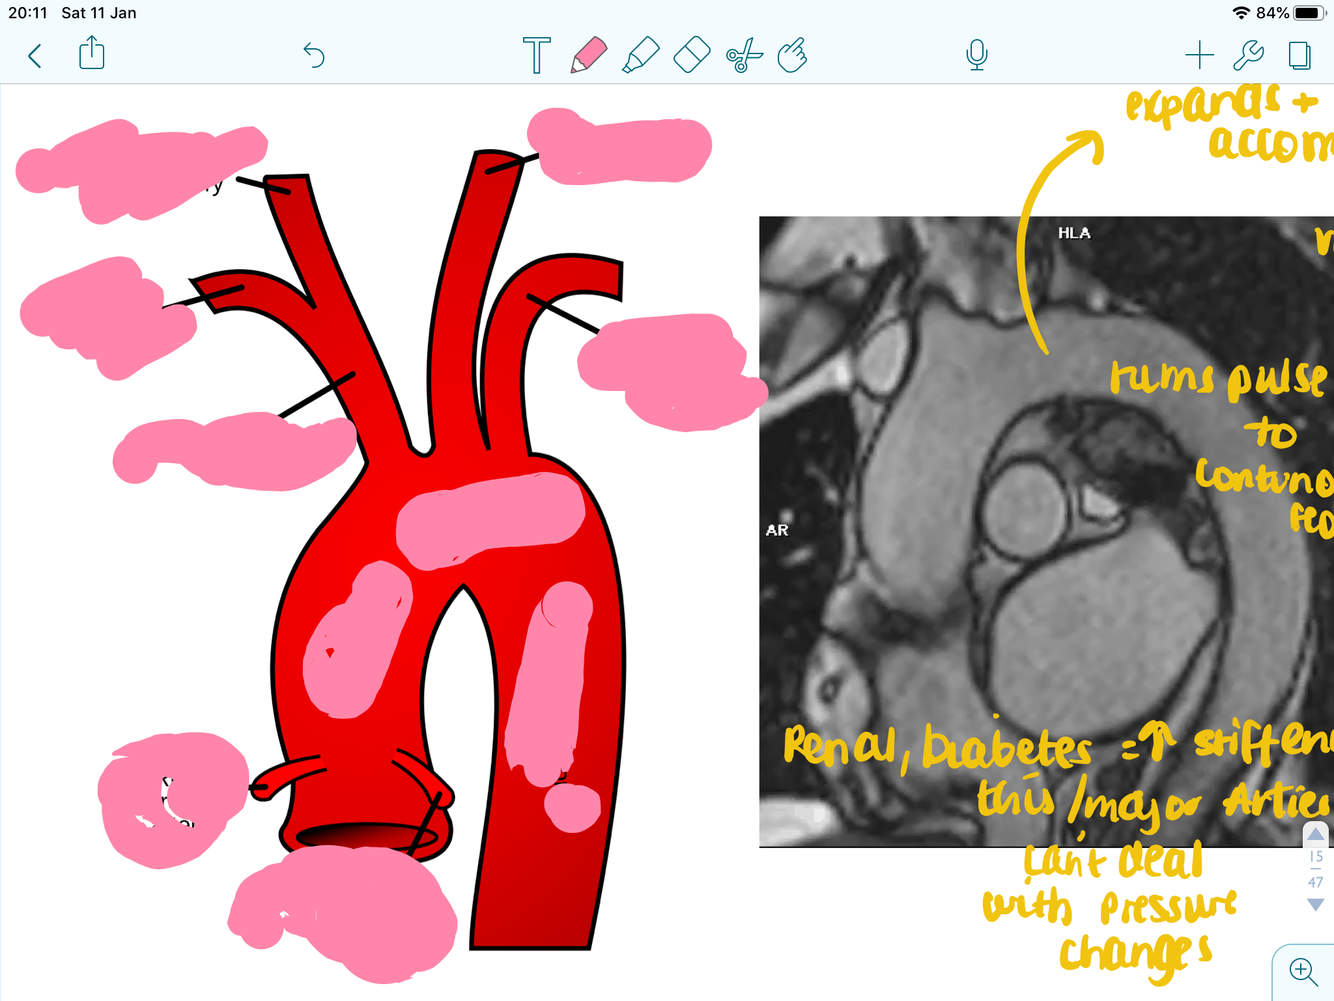

label these arteries

label

label the aorta

what can the aorta do?

expand to accomodate pressure

what doe this image show and what type of test is it?

MRI